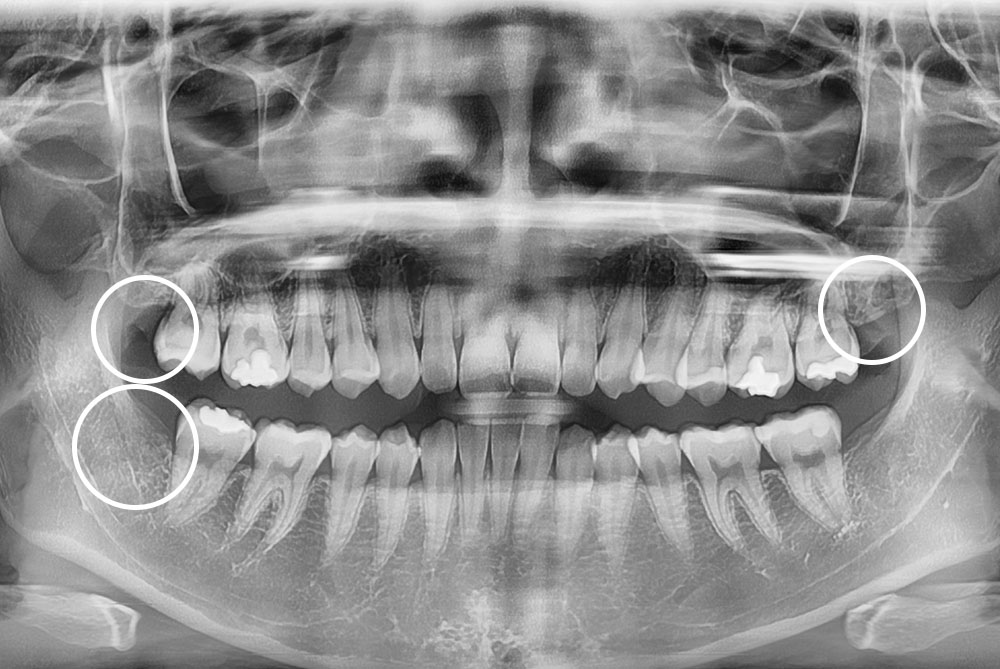

[사랑니] 매복 사랑니 발치

치료후 : 2021-11-30

세종치과는 구강악안면외과학 박사이신 원장님이 발치하는 치과입니다.